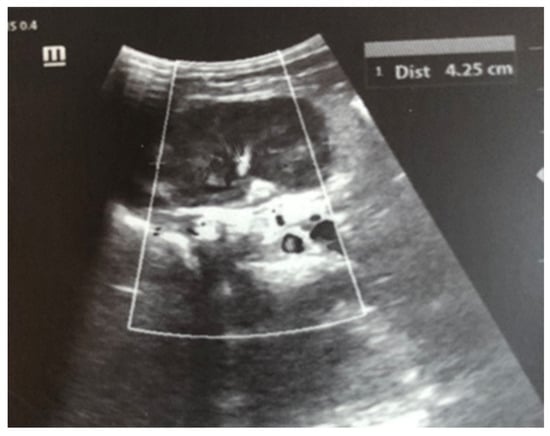

Complex therapy was performed—mechanical ventilation, antibiotics in doses adjusted according to creatinine clearance, anticonvulsants, low-molecular-weight herapin (Enoxaparin), inotropic (Dopamine), and phototherapy. The child’s condition gradually improved and he was extubated on the 9th day of the stay in the NICU. An uncomplicated post-extubation period followed. In the following 2–3 days, macroscopic hematuria was observed. On the second day after extubation, the child’s diuresis was good. The condition of the right kidney was monitored by ultrasound on the 3rd day (Figure 3), the 10th day (recovery of renal venous blood flow was observed), and at the end of the first month. On the 10th day, a decrease in kidney size was noted, and at the end of the first month, the size was below the norm for the age—i.e., the onset of renal atrophy. Follow-up examinations at 6 months and 1 year showed evidence of the atrophying of the right kidney with a longitudinal size of 2 cm, the occurrence of compensatory hypertrophy of the left kidney, normal blood pressure, and preserved renal function (Figure 4).

Figure 3. Right kidney image taken on the third day after birth—increased size, increased echogenicity of the parenchyma, and loss of cortico-medullary differentiation.